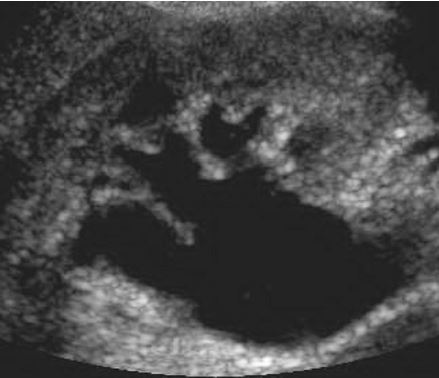

Tubular Ectasia of the Rete Testes

• The rete testes are a complex collection of small tubules that are located in the mediastinum of the testis. Fluid from the seminiferous tubules drains into the rete testis and then exits the rete testis via the efferent ductules. The efferent ductules then converge into the head of the

epididymis.

• Tubular ectasia of the rete testes is believed to be caused by some degree of outflow obstruction of the seminiferous fluid. Perhaps this is the reason why it is frequently associated with testicular cysts and spermatoceles of the epididymal head. It is also more commonly seen in patients with a history of inguinal surgery, such as hernia repairs and vasectomies.

• The key to making the diagnosis and distinguishing tubular ectasia of the rete testes from cystic testicular tumors is to note the bilateral involvement when present and to recognize the elongated shape on long-axis views of the testis.